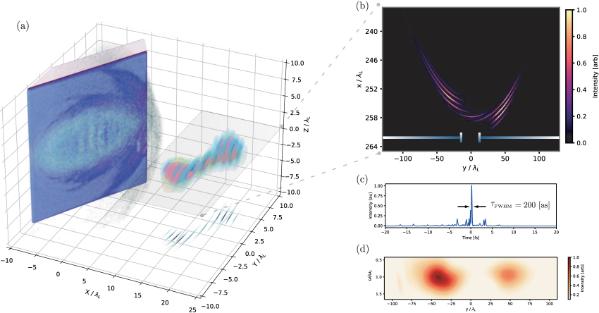

From neutron star collision to ground breaking cancer research to eco-designing for the future take a look at some of the groundbreaking studies carried out by NI-HPC users!

Carbon ion beam to enhance the precision of cancer treatment